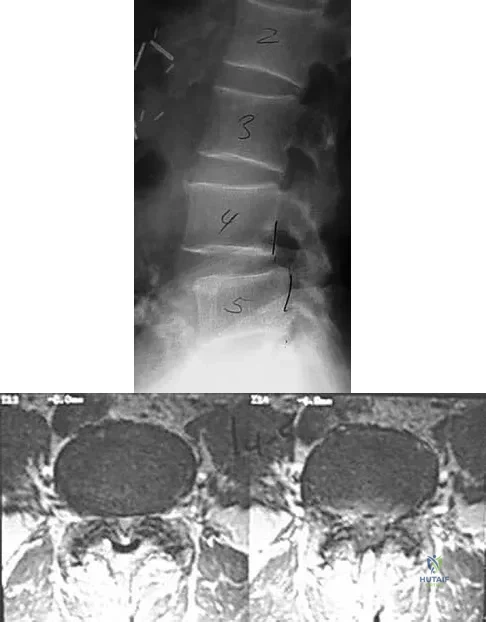

An otherwise healthy 70-year-old man has back and bilateral leg pain in an L5 distribution that is aggravated by standing more than 10 minutes or walking more than 100 feet. He has to sit to get relief. Neurologic and pulse examinations are normal. A radiograph and MRI scan are shown in Figures 4a and 4b. Treatment should consist of